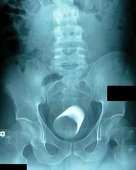

Над автором нескольких книг о войне надругалась девушка легкого поведения на юге Москвы. Путана воспользовалась беспомощным состоянием писателя и предалась с клиентом экстремальным утехам с использованием пульта от телевизора. Инородный предмет в своем теле писатель обнаружил только на второй день.

Как удалось выяснить «МК», инцидент произошел в ночь на 29 августа. 48-летний Василий (имя изменено) уже несколько дней находился в запое и вызвал к себе в съемную квартиру ночную бабочку.

Мужчина помнит, как впустил путану в жилище и как начался «сеанс» любви, а потом у него случился провал в памяти. Василий проснулся к обеду следующего дня и снова взялся за бутылку. В квартире все было на своих местах, а ночной гостьи и след простыл.

Неожиданно писатель почувствовал болевые ощущения в причинном месте и с трудом вспомнил, как незнакомая женщина предлагала ему нетрадиционные способы занятия сексом. Мужчина пришел к выводу, что проститутка воплотила фантазии в жизнь, и вызвал «скорую», но к приезду медиков он уже был сильно пьян и решил, что все происходящее ему чудится.

Василий, находясь под действием зеленого змия, отказался от госпитализации и снова заснул. Сознание вернулось к нему только утром 30 августа. На сей раз дискомфорт был более ощутим, особенно при попытке сесть. Василий хотел включить телевизор, чтобы понять, какое сегодня число и сколько времени, но нигде не нашел пульта от телевизора.

Через некоторое время он сопоставил все факты и вместо бутылки схватился за телефон, чтобы вызвать «скорую» во второй раз. Люди в белых халатах отвезли писателя в больницу, где из его прямой кишки извлекли пульт от телевизора.